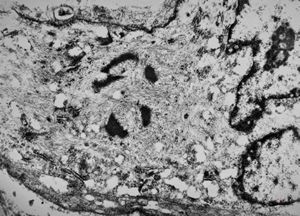

M,3y. | globoid leukodystrophy of Krabbe - n.suralis